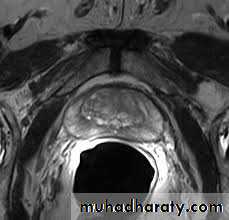

MRI and CT Scan